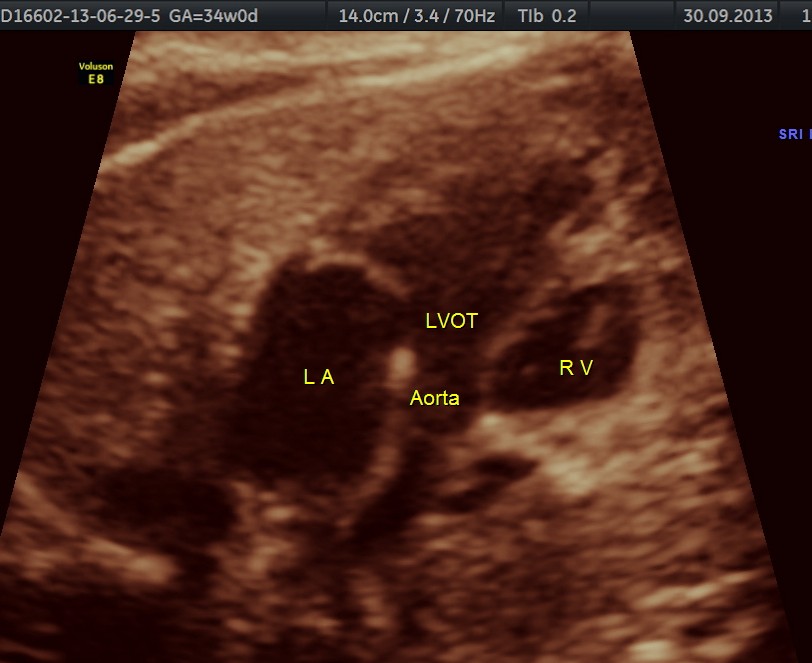

The following are of the 34 weeks gestation :

The 4 chamber view shows the patent foramen ovale. 2 pulmonary veins are also seen entering the left atrium.